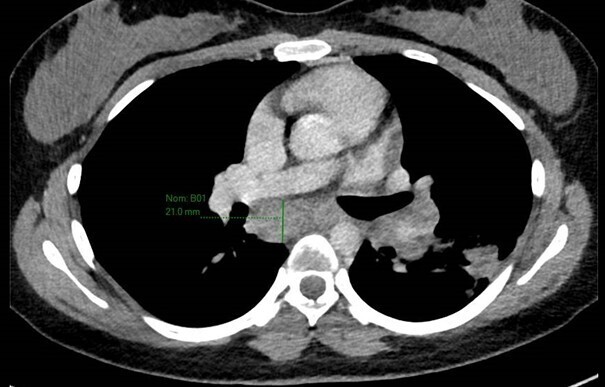

Le scanner thoracique montre des ganglions médiastinaux dont le centre est hypodense, ainsi que quelques lésions parenchymateuses en arbre en bourgeon.

Tableau évocateur de tuberculose maladie, ce qui est cohérent avec les ganglions médiastinaux nécrotiques et la topographie de l’atteinte parenchymateuse.